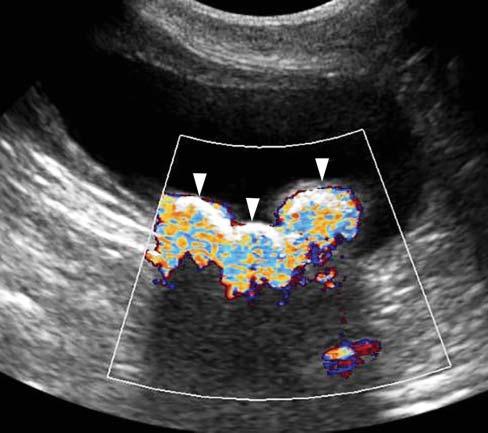

TwinklingArtifact

WhenusingcolorflowDoppler,zonesofrapidly changingredandbluehuescanbeseenbehind stronglyreflectivestructures,suchascalculiortissuemineralization(Figure1.23).Thisartifactseems independentofthecalculicomposition,anditis accentuatedbythesizeandsurfaceofthecalcification orcalculus(Louvet2006).Itcanbeencounteredwith

Figure1.23. Twinklingartifact. Severalhyperechoic interfacesassociatedwithshadowingarepresentinthe bladder,consistentwithcalculi.Whenactivatingthecolor flowDopplermode,zonesofrapidlychangingredand bluehues(arrowheads)canbeseenbehindthesestrongly reflectivestructures.

calculiinthebladder,gallbladder,orassociatedwith anytissuemineralization.